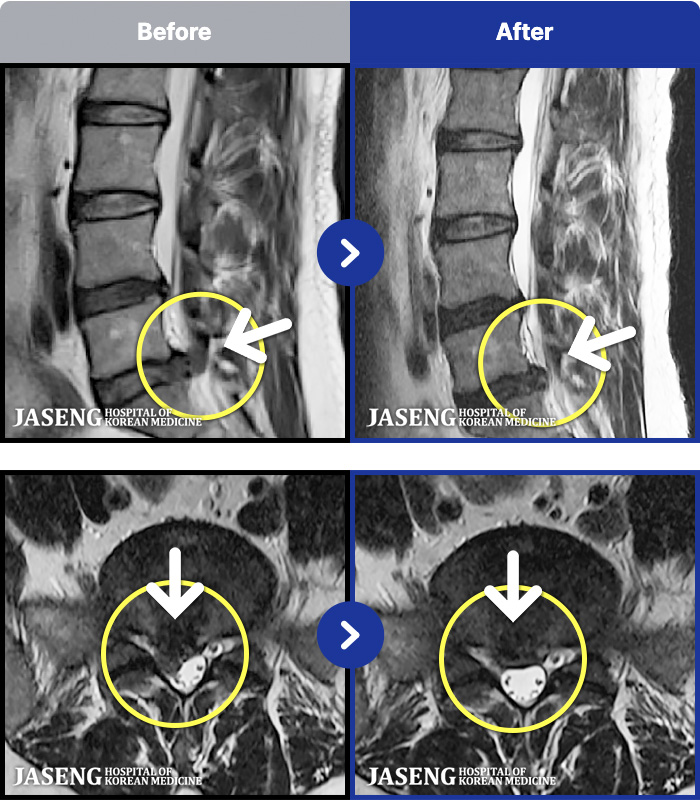

MRI ġ

MRI ũ ʸ Ȯϼ.